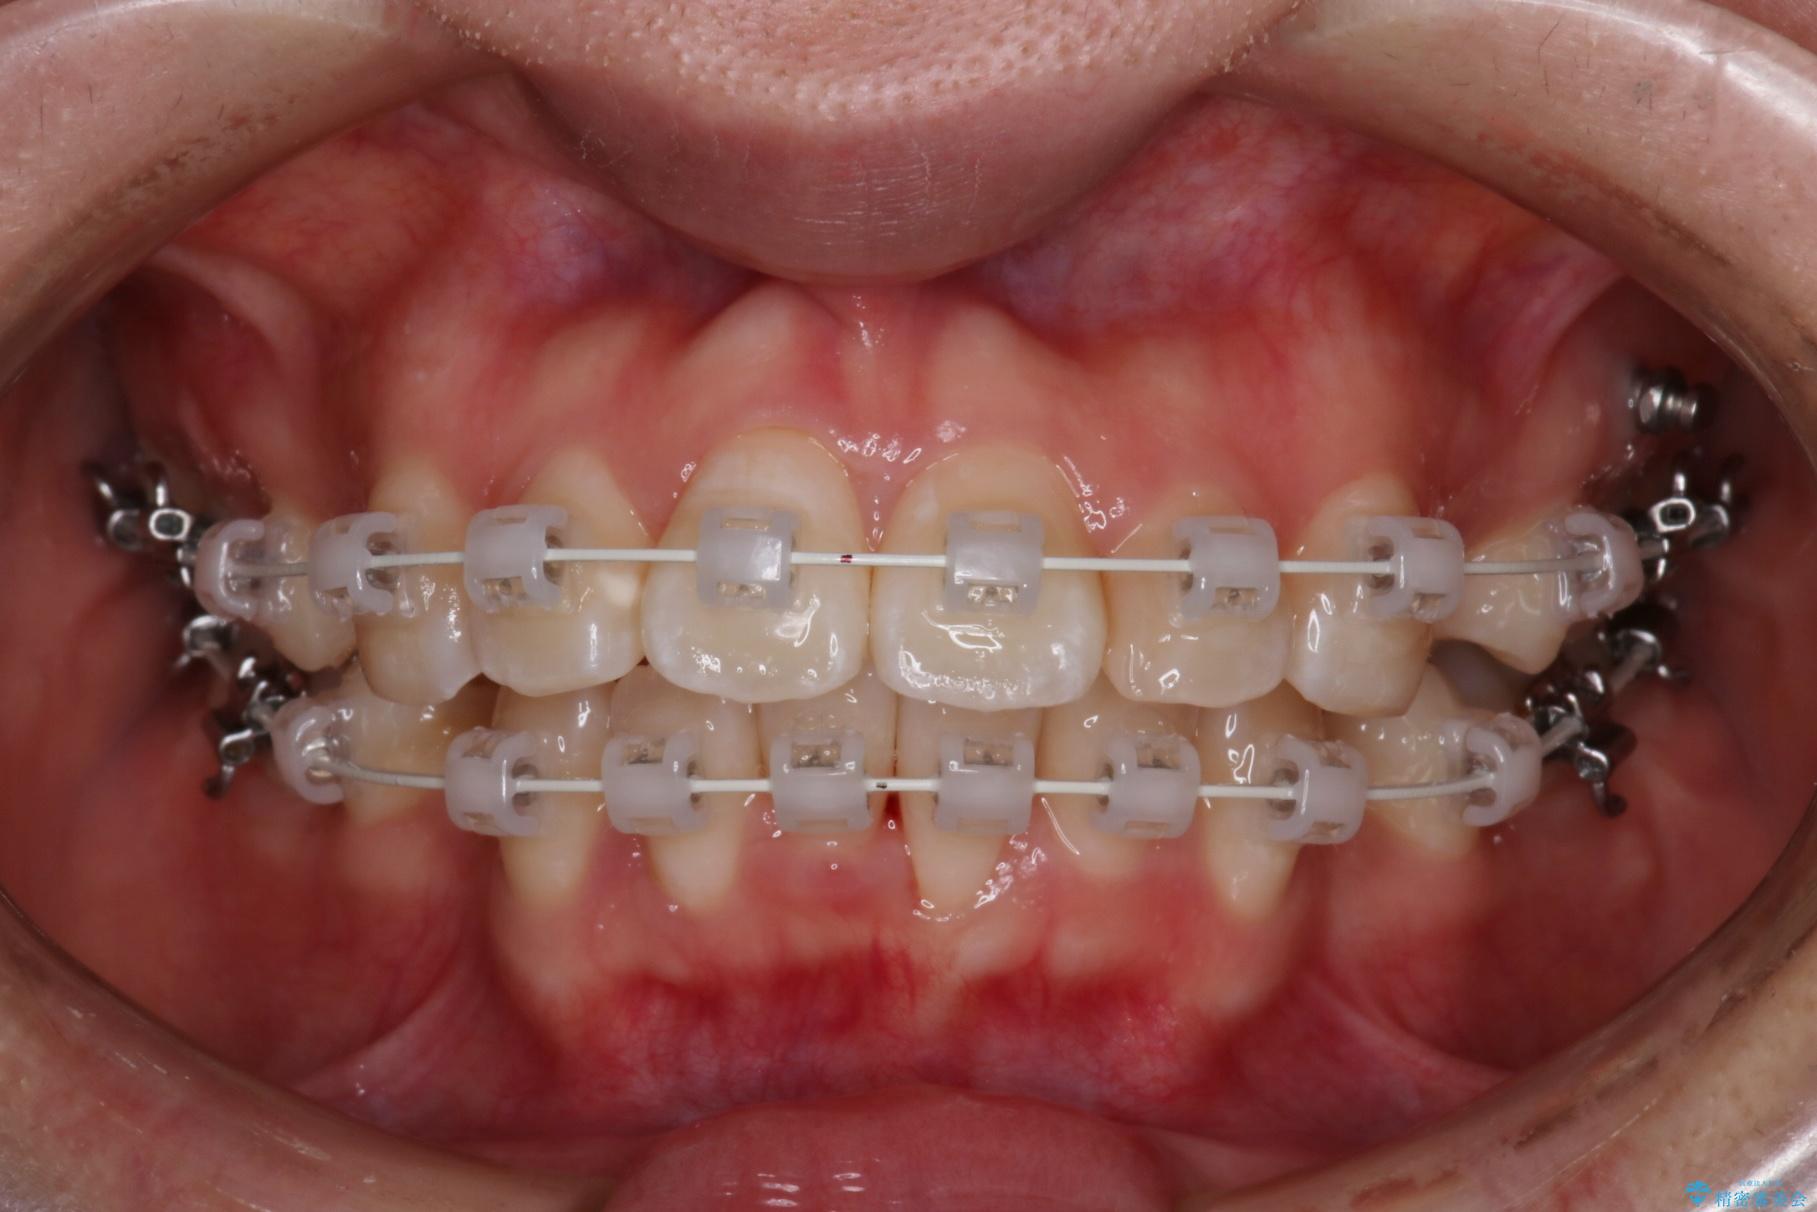

- 1年9ヶ月

上下4番目の歯を抜歯してガタつきを改善しながら口元を下げる治療計画を立てました。

抜歯矯正で口元を下げたことで、Eラインが大変綺麗になりました。

期間も1年9ヶ月と比較的短期間で治療完了することができました。